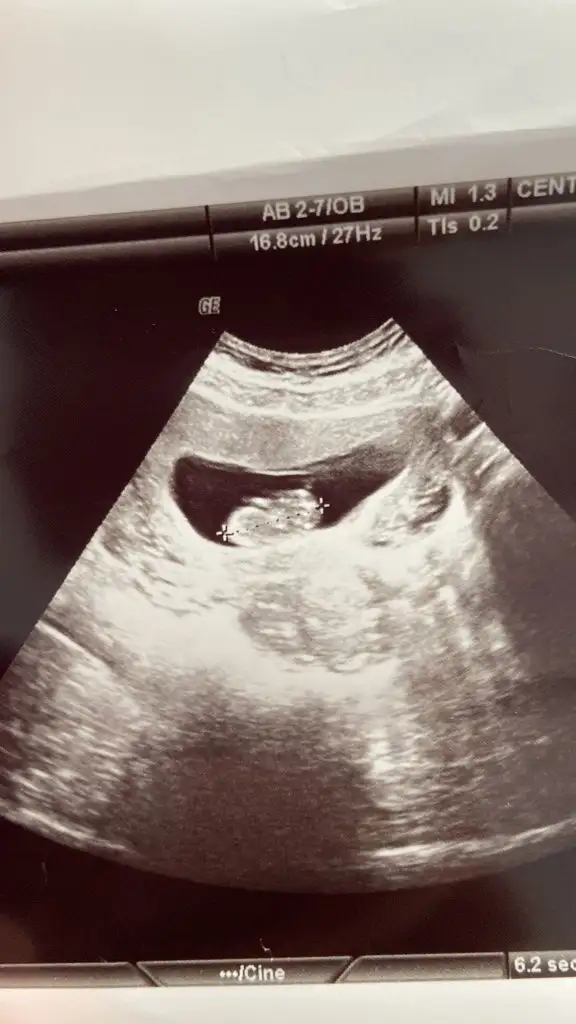

9haftalik karından bakıldı Pasha22 Pasha22 hadi kız gör bugün msji

• IMG20220609101500.webp

IMG20220609101500.webp

29,3 KB · Görüntüleme: 73